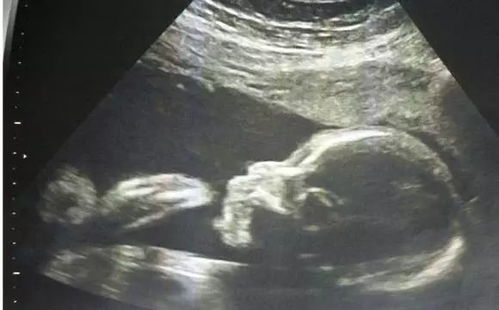

怀孕期间,定期进行胎儿系统超声检查是确保母婴健康的重要手段。24周是进行胎儿系统超声检查的关键时期,本文将详细介绍24周胎儿系统超声检查的内容、目的以及注意事项。

24周胎儿系统超声检查是孕期中期的重要检查项目,此时胎儿各个器官已基本发育成熟,通过超声检查可以全面了解胎儿的生长发育状况,及时发现潜在的异常情况,为孕妇提供科学、准确的孕期指导。

24周胎儿系统超声检查是孕期中期的重要检查项目,通过全面了解胎儿的生长发育状况,有助于及时发现潜在的异常情况,为孕妇提供科学、准确的孕期指导。孕妇应重视24周胎儿系统超声检查,积极配合医生进行相关检查。